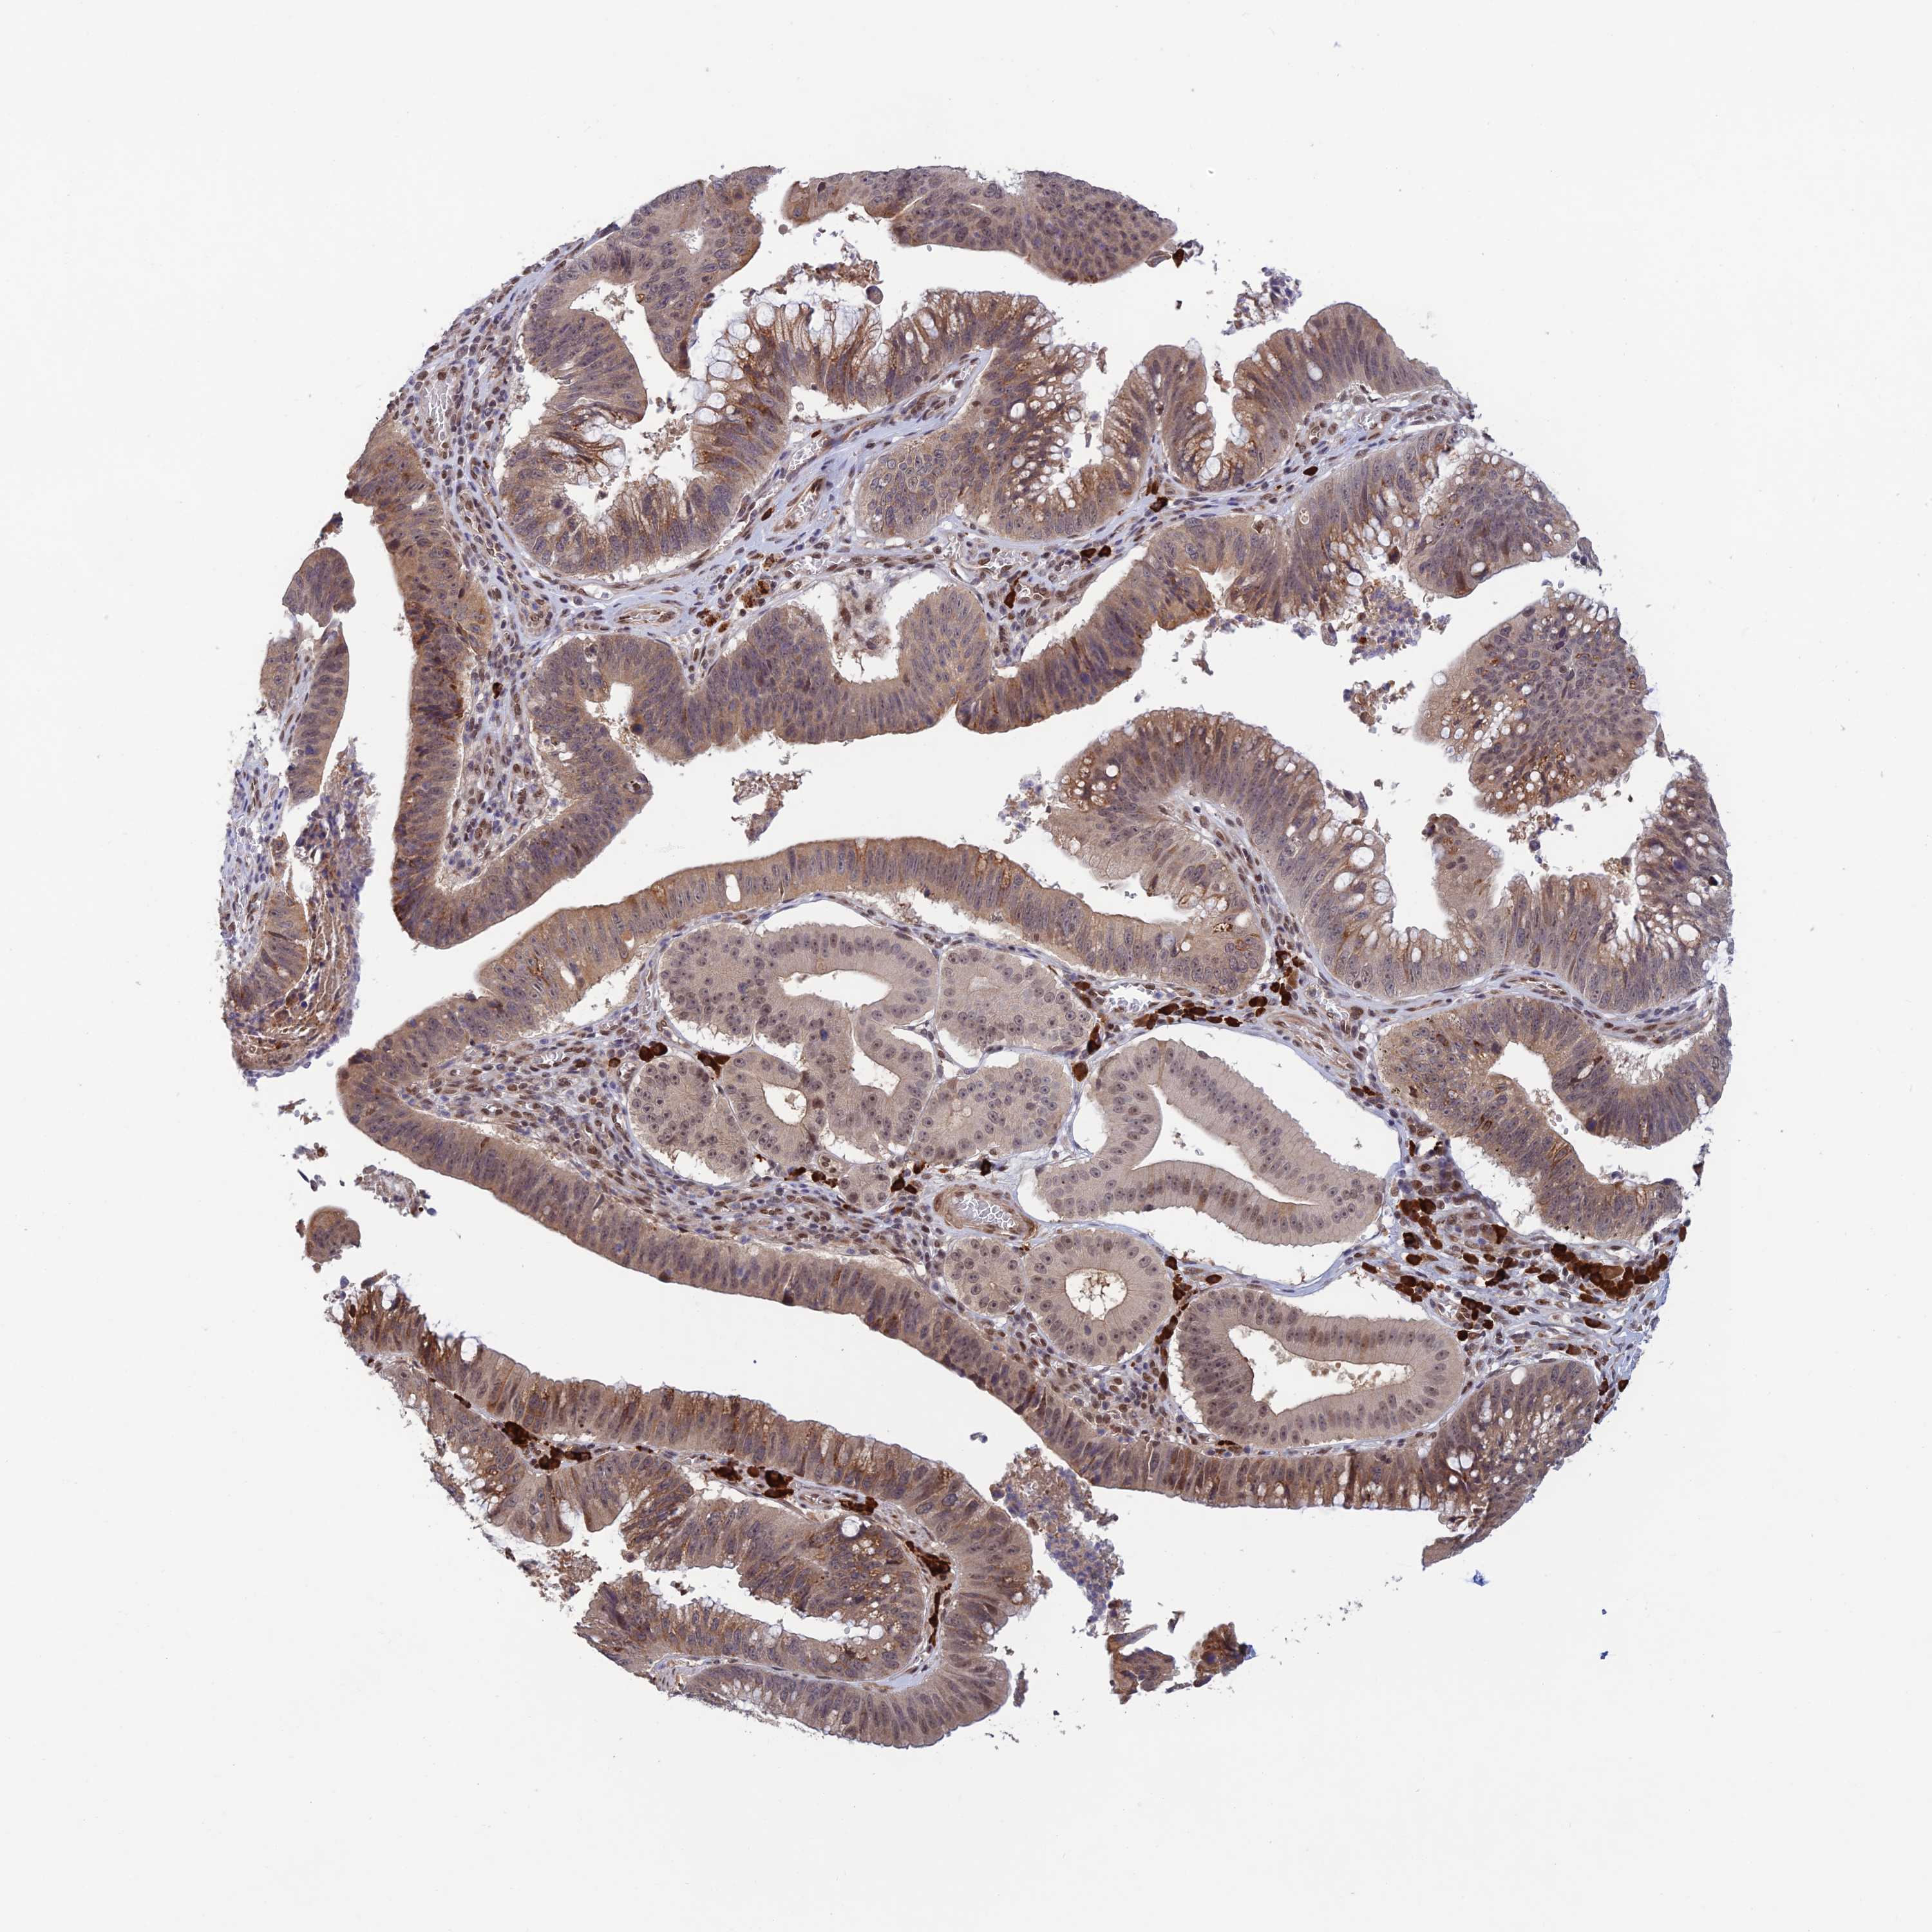

STOMACH CANCER - Protein expressioni

A mouse-over function shows sample information and annotation data. Click on an image to view it in a full screen mode. Samples can be filtered based on level of antibody staining by selecting one or several of the following categories: high, medium, low and not detected. The assay and annotation is described here.

Note that samples used for immunohistochemistry by the Human Protein Atlas do not correspond to samples in the TCGA dataset.

Antibody stainingi

Antibody staining in the annotated cell types in the current human tissue is reported as not detected, low, medium, or high, based on conventional immunohistochemistry profiling in selected tissues. This score is based on the combination of the staining intensity and fraction of stained cells.

Each image is clickable and will lead to virtual microscopy that enables deeper exploration of all samples and also displays staining intensity scores, fraction scores and subcellular localization as well as patient and tissue information for each sample.

Antibody HPA044123

Staining

High

Medium

Low

Not detected

Intensity

Strong

Moderate

Weak

Negative

Quantity

>75%

75%-25%

<25%

None

Location

Nuclear

Cytoplasmic/membranous

Cytoplasmic/membranous,nuclear

Adenocarcinoma, NOS